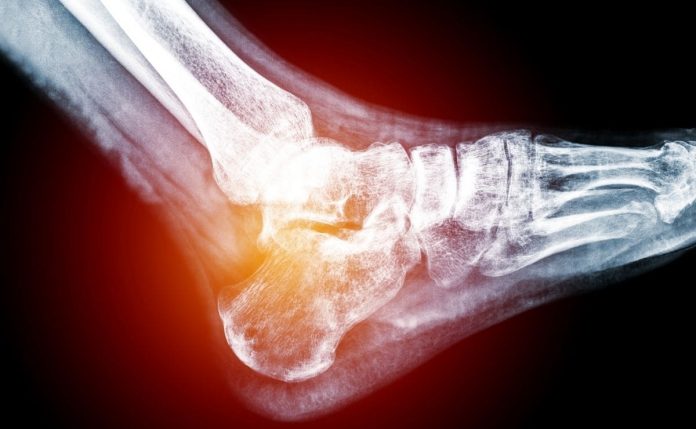

Los niveles de ácido úrico en exceso en sangre suponen un problema para la salud, pues aumentan el riesgo de desarrollar diferentes enfermedades, como la gota o cálculos renales. Además, los expertos aseguran que la hiperuricemia constituye un factor de riesgo cardiovascular por sí solo.